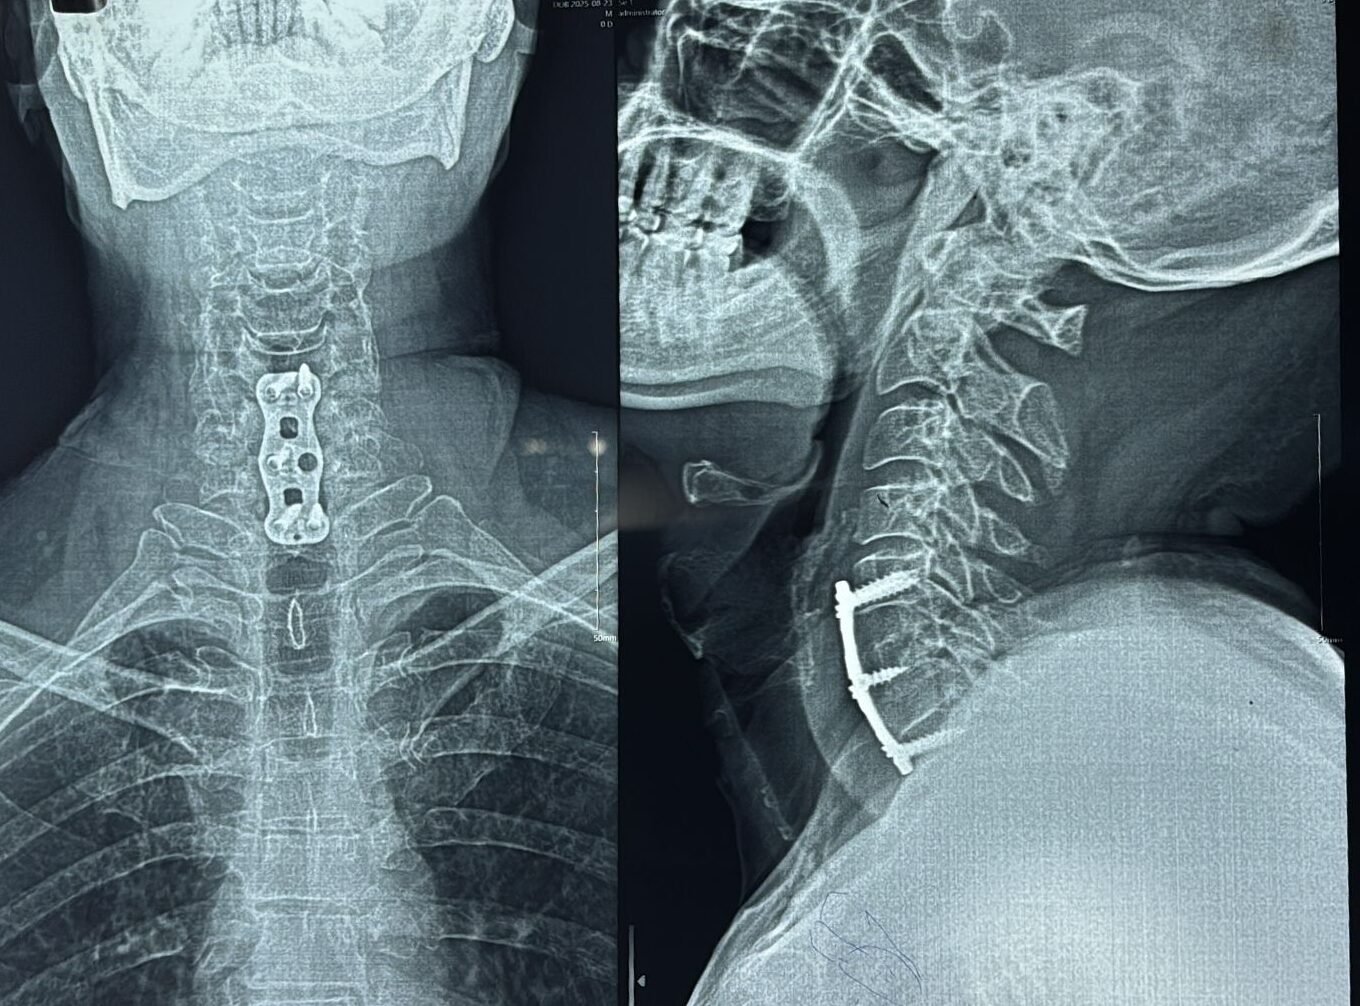

Surgery is the definitive treatment for most patients with cervical myelopathy.

- Anterior Cervical Discectomy and Fusion (ACDF)

- Cervical Corpectomy

- Posterior decompression (Laminoplasty / Laminectomy with fusion)

The choice of surgery depends on the number of levels involved, spinal alignment, and cause of compression.